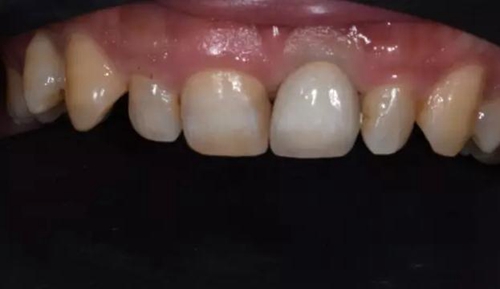

修復(fù)體試戴,修復(fù)體和原牙顏色上有輕微差異,不過患者本人非常滿意。

修復(fù)后正面口內(nèi)微笑照。